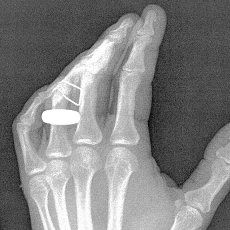

That’s what I’m doing today thanks to a relatively freak accident with a staple gun yesterday. I won’t bore you with the details (that would confirm what a bonehead I can be sometimes). Just suffice it to say that, it could have been a lot worse.